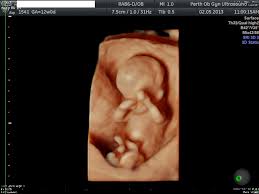

4D Ultrasound Pictures 35 Weeks - Got My 3d 4d Ultrasound At 35 Weeks Too Cute Not To Share January 2020 Babies Forums What To Expect - You'll notice that what you see varies a lot by the number of weeks of gestation.. Even if they're squished and you don't get the best pictures. They were the first to tell me that i was having a baby boy at 16 weeks. The way 4d/3d works is it sends sound waves into the uterus. Baby's first photos 112 e. The best proof is our gallery of weekly 3d ultrasound images taken from 13 weeks and until up to 39 weeks.

Baby impressions is an elective 3d 4d ultrasound imaging facility. Fetal measurements (by request) hear & see baby's heartbeat. 3d & 5d ultrasound images and 4d ultrasound video can be obtained at any stage. Baby's estimated weight and position. 30 weeks is best for 3d/4d images of what your baby will look like after it is born. Water can improve the quality of an ultrasound. At this stage, the baby has put on some weight and filled out to make features more visible, yet still enough fluid in front of baby's face to obtain great images. You'll notice that what you see varies a lot by the number of weeks of gestation. It was a very special day for my husband and i. In addition to 3d 4d ultrasound, baby bloom is known for our spectacular hd live ultrasound imaging. We do not perform medical ultrasounds. When i was 31 weeks i went back for our first 3d/4d ultrasound and it was even more special being able to see my son's face for the very first time. Book now *free rescan if face can't be seen at all.

In these final weeks before your baby's birth, several subtle changes are taking place that will prepare. 4d or 4 dimensional scans build on the technology of 3d scans. Video recording of your session on babyflix. Each week in pregnancy can look slightly different. 3d/4d & hd ultrasound 8 week baby in 2d, 3d/4d & hd ultrasound pictures 12 week baby in 3d 4d baby ultrasound pictures 15 week baby in 2d, 3d/4d & hd ultrasound pictures 23 week baby in 3d 4d & hdlive baby pictures 13.5 weeks 14 weeks 15 weeks 15.2 weeks twins 16 weeks 18 weeks 22 weeks 24 weeks 27 weeks 29 weeks 30 weeks 31 weeks with.